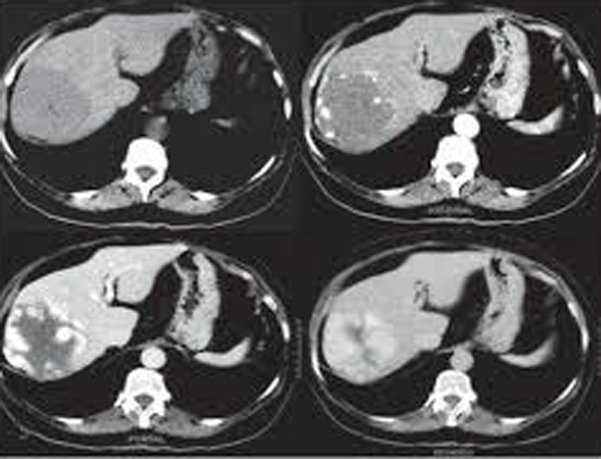

Kỹ thuật xạ hình chẩn đoán xuất huyết tiêu hóa là một phương pháp chẩn đoán hình ảnh được sử dụng để xác định nguyên nhân của xuất huyết đường tiêu hóa. Phương pháp này sử dụng hình ảnh chụp từ máy quét để tạo ra hình ảnh chi tiết của đường tiêu hóa và phát hiện ra các vị trí xuất huyết. Kỹ thuật xạ hình chẩn đoán xuất huyết tiêu hóa thường được thực hiện bằng cách tiêm chất đánh dấu vào tĩnh mạch và chụp hình sau đó để xem chất đánh dấu lưu thông trong đường tiêu hóa.